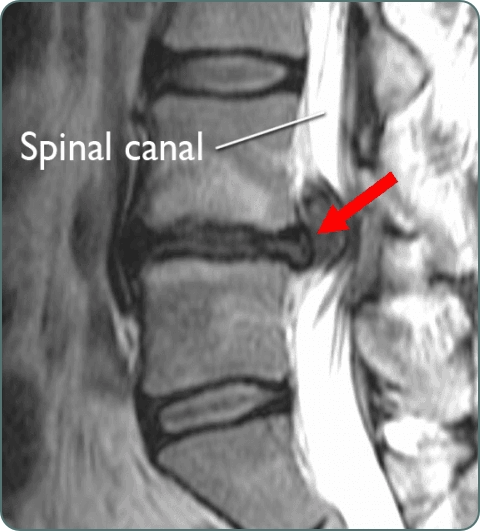

Spinal Stenosis

Narrowing of spinal canal causing pressure on spinal cord and nerves. Results in pain, numbness, and difficulty walking requiring decompression surgery.

MRI Spine

High-resolution imaging of spine and spinal cord to evaluate discs, nerves, and soft tissues. Essential for diagnosing spinal conditions.